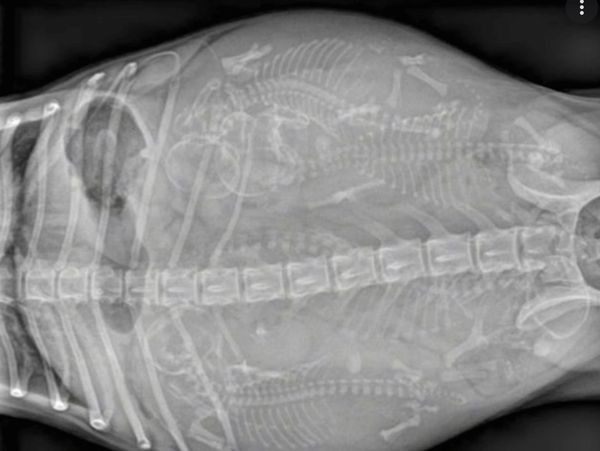

We utilize the most accurate technique in determining confirmation of pregnancy. After day 35 we offer Ultrasound confirmation ( $75). After day 45 we offer radiograph ( $135includes as many views as necessary and all views are emailed directly to you).

High resolution digital radiography is now available and can safely be performed at 42 days of pregnancy to confirm and count number of fetuses .